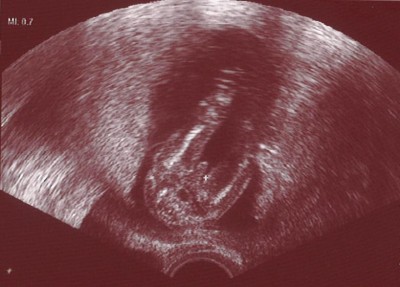

Ich war heute morgen zum 1. US des Zyklusmonitoring und war einerseits zwar sehr positiv überrascht, mit wieviel mehr Respekt einen der neue Arzt behandelt und wieviel mehr er einem erklärt. Leider gab es andererseits aber nur unschönes zu erklären. Auf dem US sah man leider ganz deutlich, dass meine Eierstöcke viel zu groß sind und sehr viele kleine Follikel am Rand haben, was zusammen mit dem erhöhten Testosteron dann doch heisst, dass ich PCO habe. Das alleine ist ja schonmal nicht so schön, weil ich die Hoffnung auf eine spontane SS damit wieder begraben kann. Außerdem gab es aber auch noch die Blutwerte vom 2. ZT und da kam dann für mich die wirklich unschöne Überraschung, dass der FSH-Wert zu hoch sei und von einer herabgesetzten Eizellreserve ausgegangen werden muss. Leider hat sich der Arzt noch nicht wirklich über die Bedeutung der Befunde für das weitere Vorgehen ausgelassen, da er erstmal den gesamten Zyklus und die weiteren US und Blutentnahmen abwarten will. Ich denke zwar nicht, dass das heisst, dass ich innerhalb kürzester Zeit mit der Menopause rechnen mus, aber mit 29 find ich so eine Aussage, dass der FSH-Wert zu hoch sei, schon heftig. Wie ihr Euch denken könnt, bin ich jetzt jedenfalls ordentlich durch den Wind und habe mal wieder jegliche Hoffnung verloren...